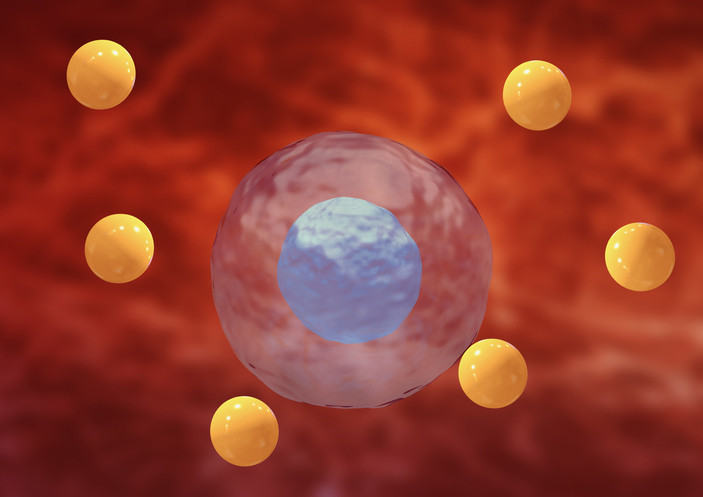

Antioksidanlar, kısaca vücutta serbest radikaller adı verilen zararlı gevşek oksijen moleküllerini nötralize edebilen bileşikler olarak tanımlanıyor. Serbest radikaller etkisiz hale getirilmediğinde sağlıklı hücrelere yapışarak oksidatif stres adı verilen bir tür hücresel hasara neden olabiliyor.

Oksidatif stres, kararsız moleküller olan serbest radikallerin vücut üzerinde yarattığı zararlı etkilere deniyor. Serbest radikaller, doku hasarına neden olabilen zararlı oksijen hücreleri. Antioksidanlar da bu zararlı hücrelerle savaşmaktan sorumlu.

Doku hasarı, kişiyi kalp hastalığı, kanser, Alzheimer ve diyabet gibi birçok potansiyel rahatsızlığa karşı daha savunmasız hale getirebiliyor. Neyse ki, meyve ve sebzeler gibi antioksidan açısından zengin besinler ve tarçın tüketerek oksidatif stresi azaltmak ve yaşamı sınırlayan hastalık ve rahatsızlıklara yakalanma riskini düşürmek mümkün.